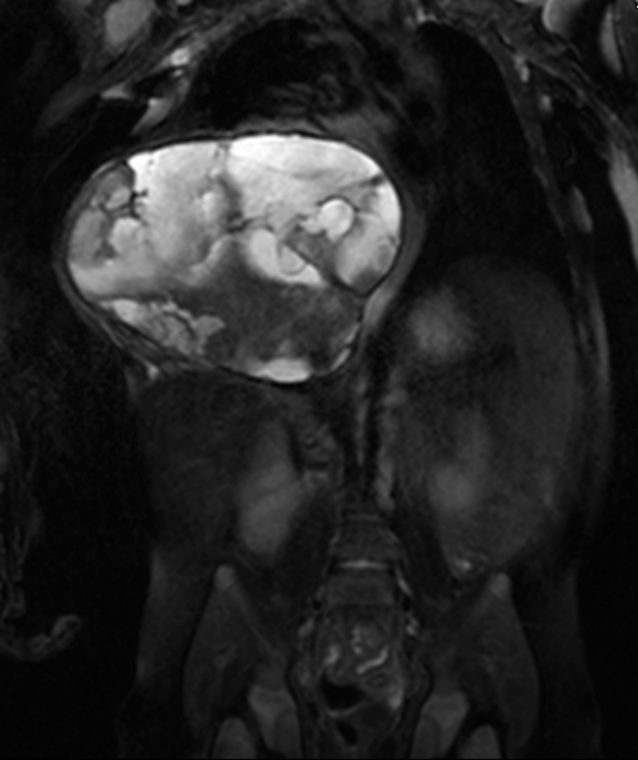

In the course of the follow up examination at 5 weeks of age we noticed an anemia with the necessity of a transfusion (Hemoglobin 6.8 g/dl). The condition of the child worsened dramatically. The MRI disclosed an increase in size to 9.3 x 8.1 x 7 cm due to hemorrhage. This enlargement was accompanied by shifting the large vessels to the left side and compressing the inferior vena cava. Sedimentation levels within the large cystic spaces of the hamartoma indicated intralesional bleeding (Figure 3 [Fig. 3]).

Figure 3: Large intrathoracic extension of the midline crossing tumor